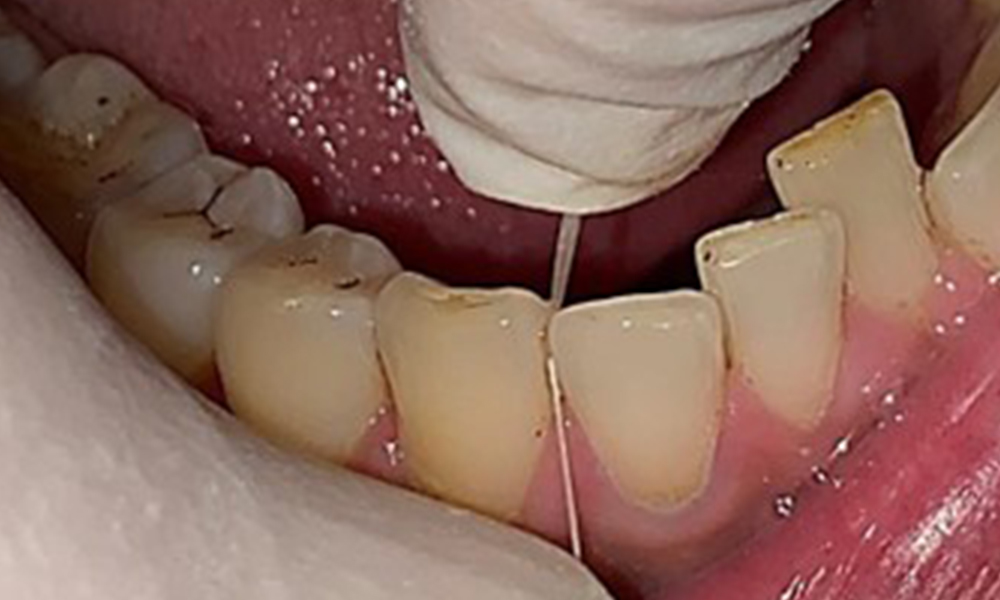

Dentaler Befund

Dental zeigt sich ein vollbezahntes Gebiss mit 28 Zähnen. Auffällig sind Erosionen und Attritionen

(Abb. 4, Abb. 5). Der Patient trägt seit vielen Jahren nachts eine Schiene mit adjustiertem Aufbiss aufgrund Bruxismus. Die Erosionen sind auf den langjährigen Konsum isotonischer Getränke zurückzuführen. Parodontaler Knochenverlust und aktive kariöse Läsionen sind nicht vorhanden.